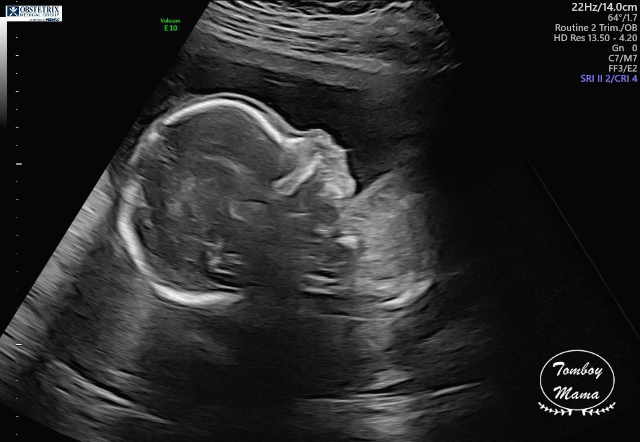

여기서 잠깐 보고 가는 튼튼이 20주차 (정확히는 19주 6일차) 초음파 사진들!

(1) 태아도 건강하고, 크기도 딱 좋고 (하루만큼 더 커서 20주 0일 크기), 다 좋단다.

(2) 단, 태아의 뇌에 낭종(choroid plexus cyst)이 있는데, 주로 다운증후군과 연관이 있는 증상이라고 했다. 자연스럽게 사라질 수도 있는 거고, 아이큐에 영향을 준다던가 하는 그런 문제가 아니기 때문에, 이게 발견되었다고 나중에 따로 추적하지는 않는다고 했다. 다만 다운증후군 가능성이 염려되면 (바늘로 찔러서 하는) 양수 검사를 할 수 있는데, 솔직히 지금 나에게는 추천하지 않는다며 3가지 이유를 얘기했다.

a. 정밀 초음파 검사 결과 이 외의 다른 증상이 보이지 않고, 모두 정상으로 보임.

b. 아기의 크기가 정상적으로 잘 자라고 있음.

c. NIPT 및 NT 테스트 결과가 이미 음성이었음.